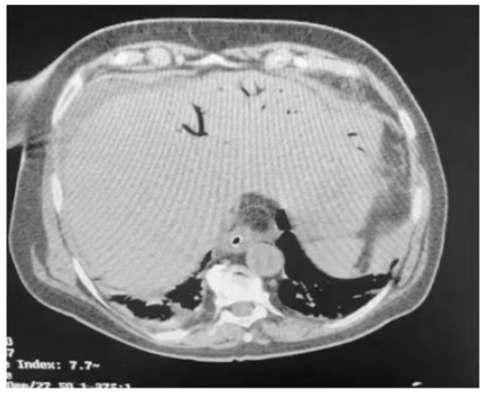

Um paciente de oitenta anos de idade, já com grau de perda de funcionalidade, com períodos de esquecimento, chegou ao pronto-socorro com queda importante do estado geral, com poucas informações objetivas, porém com dor ao exame físico de abdômen. Difícil interpretação dos sinais de irritação peritoneal. Realizou a tomografia abaixo.

Enunciado 3313718-2